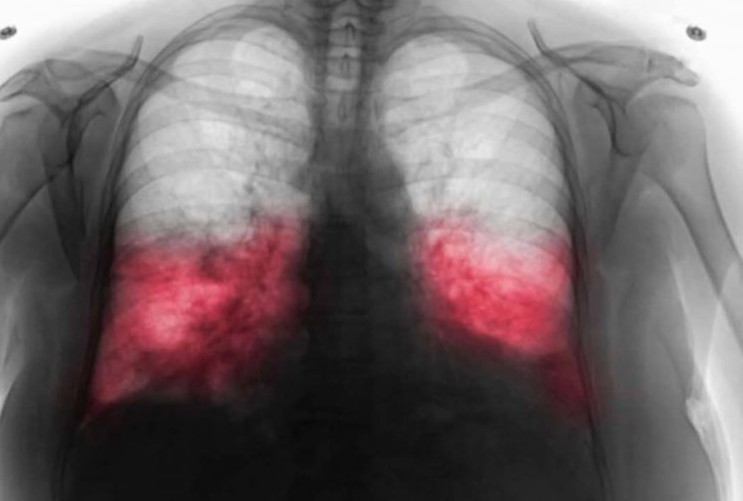

Ako sumnjate na hodajuću upalu pluća, važno je odmah se obratiti ljekaru. Ljekar će obaviti detaljan pregled, uključujući laboratorijske testove i, ako je potrebno, rendgenski snimak pluća. U nekim slučajevima, može se uzeti bris iz dišnih puteva kako bi se precizno utvrdio uzročnik. Hodajuća upala pluća zahtijeva specifične antibiotike, jer uobičajeni antibiotici često nisu dovoljni za liječenje. Odlaganje posjete ljekaru može rezultirati pogoršanjem stanja i produženim vremenom oporavka, što može biti posebno opasno za najosjetljivije grupe.